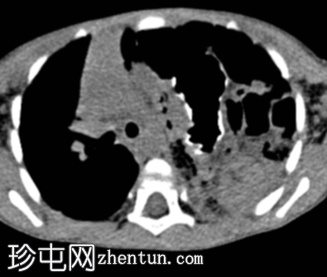

矢状面C+期

动脉期

左侧膈疝通过位于左膈中部的一个缺损形成,伴有纵隔向右侧移位,下方左塌陷。

脾脏、大肠和小肠均有疝气,同时伴有肠系膜上血管疝气。

胃位于下部,靠近主动脉分叉处。

在降结肠和直肠中可见先前荧光透视检查的残留造影剂。